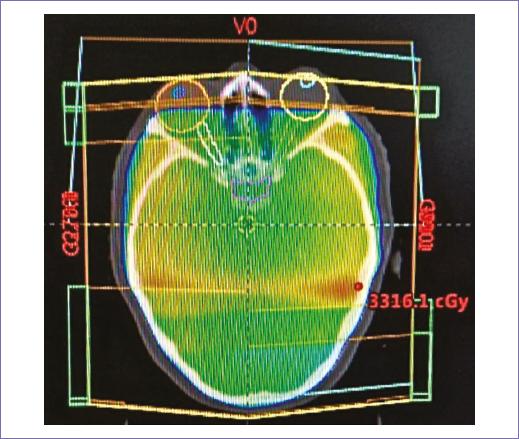

Recibió radioterapia adyuvante 50 Gy/25 fracciones, con técnica 3D conformal con campos tangenciales y axilosupraclavicular (Fig. 2); la toxicidad desarrollada durante el tratamiento fue radiodermitis grado I. Durante el seguimiento, siete meses después se documentó mediante tomografía con emisión de positrones dos nódulos pulmonares con hipermetabolismo, maximum standardized uptake value (SUVmax) 3.7 y 2.8, así como trombos en la vena pulmonar izquierda, arterias ilíacas comunes y externas. Un mes después, la paciente empezó con cefalea holocraneana con intensidad del dolor en escala visual analógica 8/10, por lo que se documentó con estudios de imagen una lesión intraaxial frontal izquierda de 50 x 42 mm, de características metastásicas (Fig. 3), motivo por lo que se consideró candidata a tratamiento quirúrgico, seguido de irradiación a holocráneo 30 Gy/10 fracciones (Fig. 4). Durante el último tratamiento presentó dificultad respiratoria súbita y se documentó tromboembolia pulmonar bilateral metastásica, motivo de fallecimiento (Fig. 5).

Figura 2 Plan de tratamiento conformal, con dos campos tangenciales y axilosupraclavicular, dosis prescrita de 50 Gy en 25 fracciones.

En relación a la radioterapia, los estudios que describen esta modalidad de tratamiento son fase II, algunos autores reportan un posible beneficio con el uso de radioterapia postoperatoria en todos los sarcomas mamarios, mientras que otros demuestran resultados contradictorios, por lo que el beneficio de la radioterapia adyuvante es controvertido15-17. La irradiación después de una resección R0 debería ser considerada de acuerdo con el riesgo de recurrencia: alto grado y tamaño mayor a 5 cm, con el objetivo de incrementar el control local. Este tratamiento después de una resección R1 está recomendado en todos los casos debido a la alta tasa de recurrencia, de hasta un 60% en algunas series. Un protocolo común es aplicar una dosis de 50-60 Gy con fracciones de 2 Gy a toda la mama/parrilla costal y posteriormente un boost (incremento de dosis) para prescribir 60 Gy al lecho tumoral. En pacientes con R2 operable se recomienda cirugía nuevamente3. En el caso que presentamos, se decidió administrar radioterapia adyuvante; por el tamaño de la lesión, el grado y el hecho de ser una recurrencia, la dosis prescrita fue de 50 Gy en 25 fracciones, con un fraccionamiento convencional, con técnica conformal de 3 campos: tangenciales y axilosupraclavicular. Finalmente, de acuerdo a la historia natural de la enfermedad la paciente presento diseminación hematógena y falleció por complicaciones pulmonares.